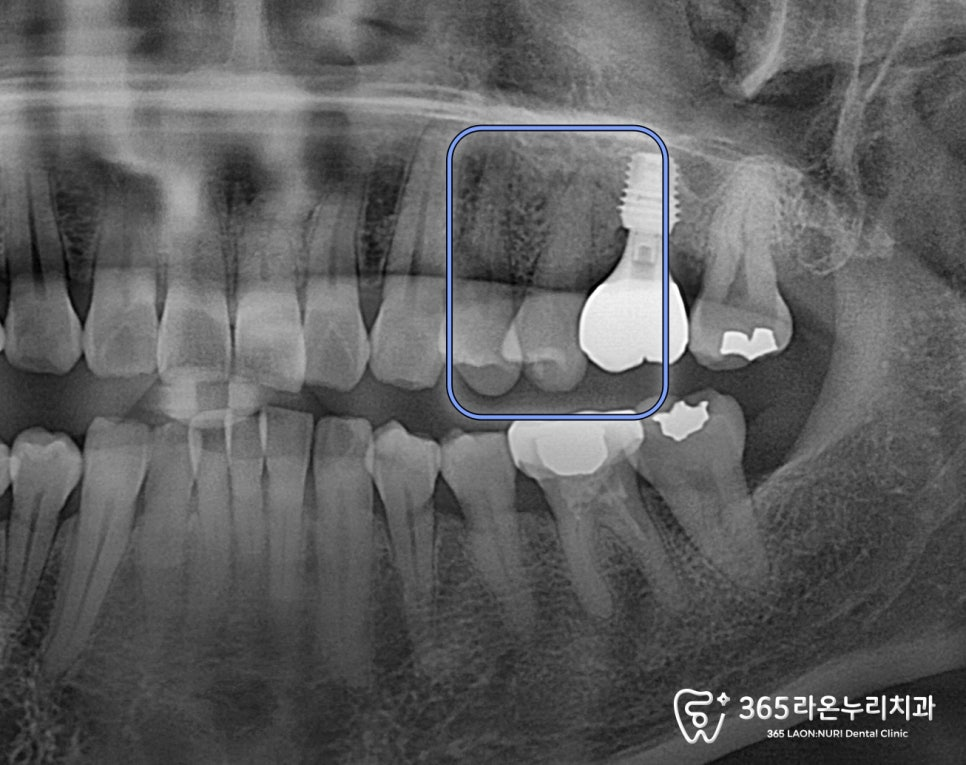

파노라마 엑스레이와

2025.4.29

큐레이 검사를 통해

수직치근파절인걸 확인했는데요.

수직치근파절은 발치하지 않으면

추후 치조골 소실, 주변치아에 안좋은

영향을 줄 수 있어

발치 후 임플란트를 해야 됩니다.